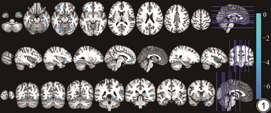

与放疗前相比,NPC患者在放疗中颞叶(双侧梭状回、右侧颞上回、右侧颞中回、右侧颞下回)、枕叶(左侧舌回、右侧矩状回)、额叶(左侧眶部额中回、左侧眶部额下回)、边缘叶(左侧岛叶、双侧前扣带回)、左侧小脑灰质体积减小(cluster水平FWE校正,P<0.001)(图1,表1)。

放疗中与放疗前相比灰质体积减小的脑区

Brain regions with reduced gray matter volume during radiotherapy compared to before radiotherapy